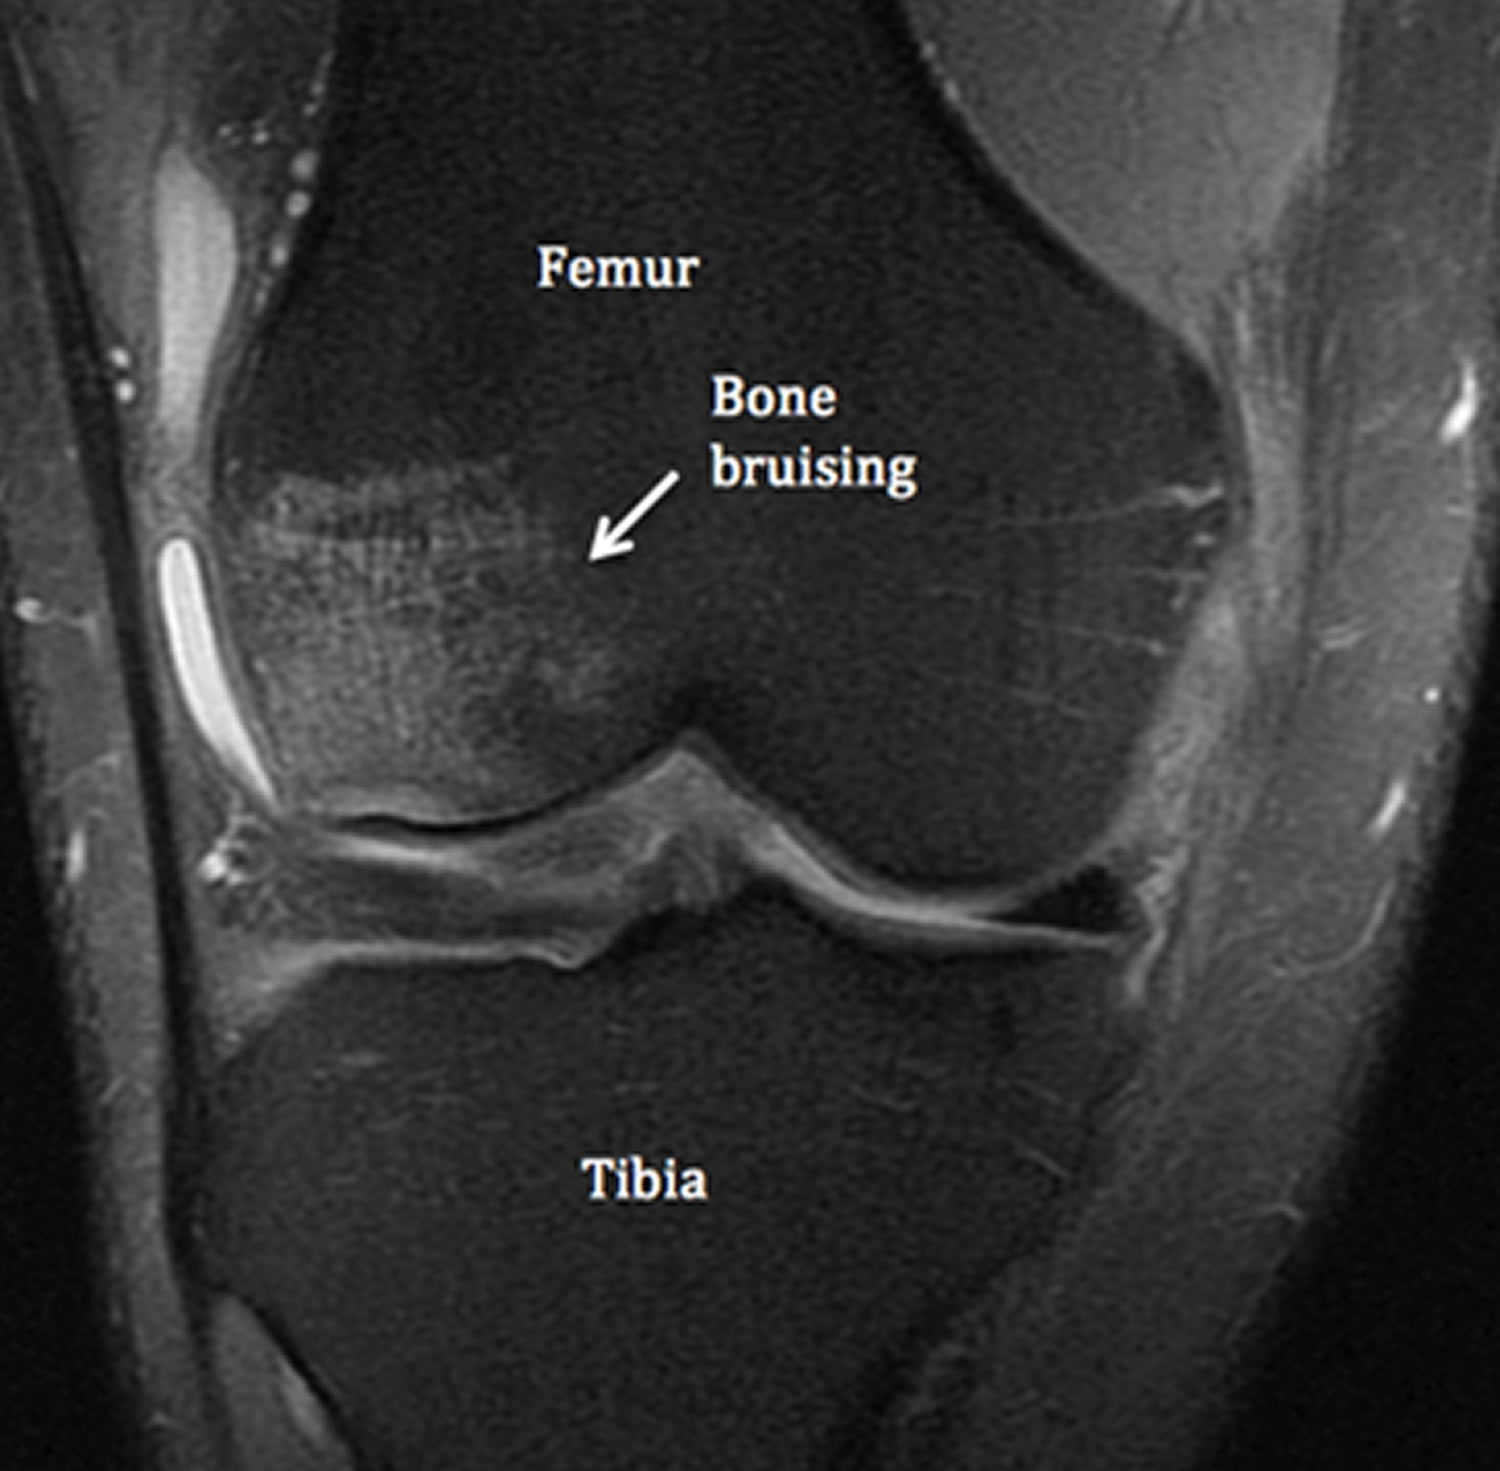

Discover the common causes of bruising of the fingers, ranging from minor trauma and sports injuries to underlying medical conditions. Learn how to identify symptoms, manage discoloration and swelling, and determine when to seek professional medical advice for finger contusions or blood vessel damage. Get the expert insights you need to treat finger pain and promote faster healing today.